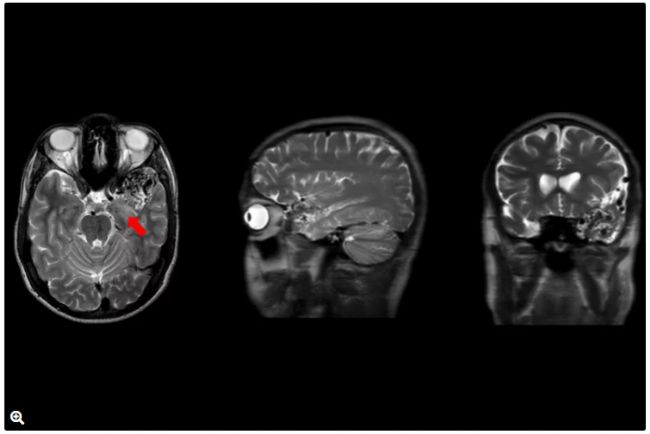

4.術后

圖9:T1加權MRI圖像,顯示AVM病灶完全切除(紅色箭頭)。

圖10:T2加權MRI圖像,顯示AVM切除后左側海馬正常信號(黃色箭頭)。

圖11:術后腦血管造影:AP投影顯示無

早期引流靜脈或殘余AVM(紅色箭頭)。

圖12:術后腦血管造影:側位投影顯示無早期引流靜脈或殘余AVM。